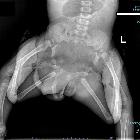

- ischiopagus: pelvis ~5%

Radiographic assessment